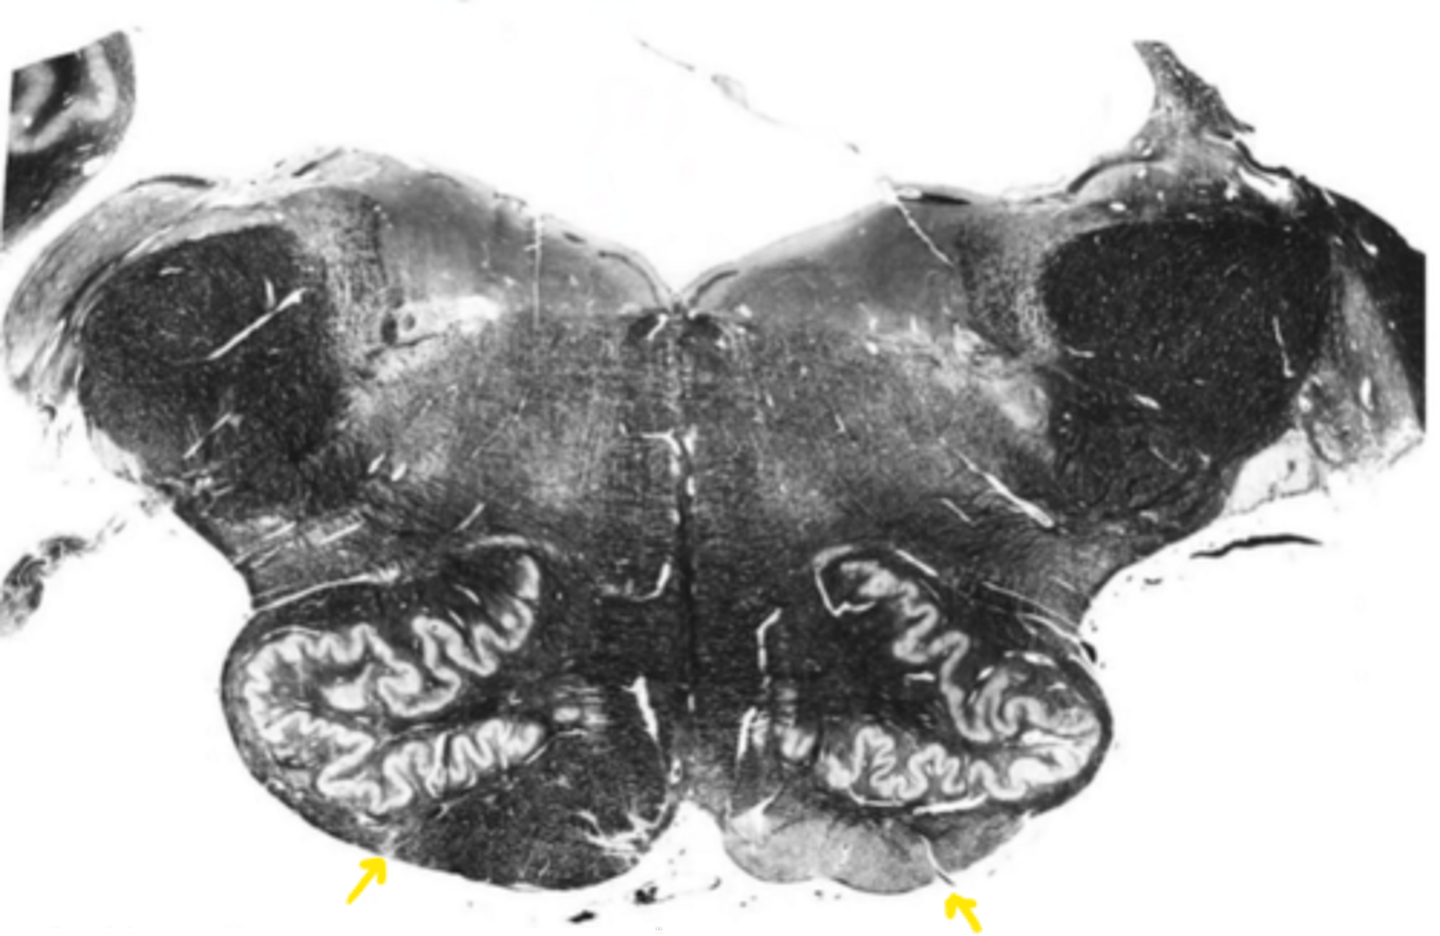

open medulla

ID the brainstem level